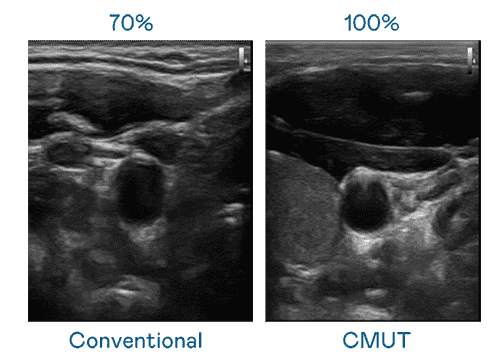

CMUT 技术是一种用电容式微机电元件来产生超音波讯号的技术。。与传统 PZT 压电式技术相比,,CMUT 频宽增加 30%,,,,更宽频的超音波讯号让影像解析度大幅提升,,,,是实现高影像品质医疗超音波扫描、、促进精准医疗发展的关键技术。。。。

大频宽带来超清晰影像

超音波影像的解析度高低,,首先取决于探头能发出的讯号频宽。。NG大舞台 CMUT 可提供高清晰的超音波讯号,,,,提供高频宽、、、、高灵敏度、、影像纹理细节更高的超音波影像,,,,协助医护人员缩短影像判读时间及利用精准的医疗影像进行诊断。。。